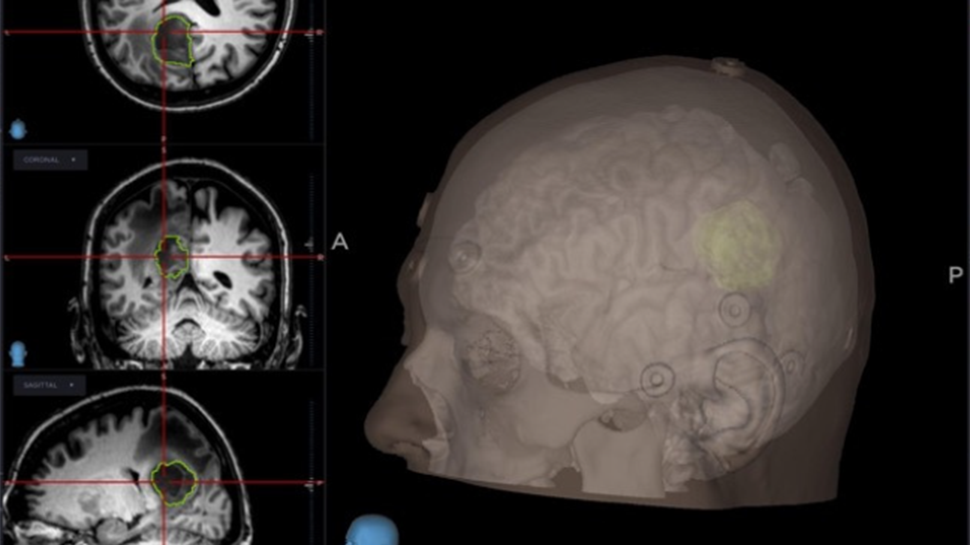

Cada procedimiento requiere una planificación meticulosa basada en estudios de imagen avanzados, con el objetivo de intervenir de manera precisa y segura, minimizando riesgos y preservando la función neurológica del paciente.

Se emplean técnicas quirúrgicas modernas, apoyadas en tecnología de alta precisión, que permiten abordajes más controlados y resultados clínicos más favorables.